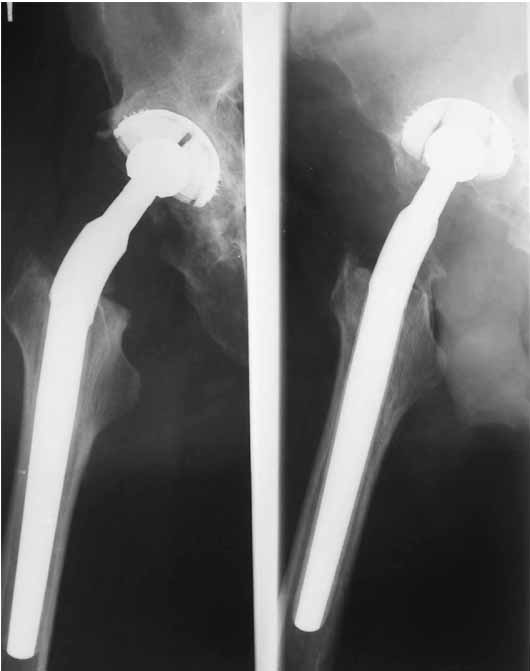

Дорогие коллеги.Мой хороший товарищ, сам травматолог-ортопед, прооперирован 1,5 мес назад. Естественно, начались проблемы. Хотелось бы узнать ваше мнениеи, главное,что делать дальше... Итак:Мужчина 50 лет.Д-з: Посттравматический деф.артроз правого тазобедренного сустава с выраженным болевым синдромом, стойкой комбинированной контрактурой иукорочением 3 см. Анамнез: 10 лет назад - сочетанная травма головы, груди, конечностей, таза... перелом заднего края вертлужной впадины и вывих бедра справа.Лечился консервативно. 25.05.94 - операция тотальное эндопротезирование правого тазобедренного сустава бесцементным эндопротезом (чашка Споторно 52, ножка Вагнера 225/21, головка L), дополнительная фиксация в кокситной гипсовой повязке в течение 3 нед. Спустя месяц после операции при поворачивании на бок в кровати произошел вывих головки эндопротеза. Под наркозом вывих вправили. Вот 10 дней лежит в постели. Что необходимо делать? Рентгенограммы до операции и после. Рентгенограммы в положении вивиха у меня отсутствуют. Ну наверное они и не столь важны, ведь вывих-то вправили. Учреждение и фамилию пациента, нашего коллеги, называть не буду. Он попросил меня собрать мнения - как ему жить дальше. Заранее благодарен. С уважением Александр Артемьев

Первые впечатления:

1. Вертикальное положение чашки;

2. Нарушение угла антеверсии ножки (судя по изображению малого вертела

на послеопреационной рентгенограмме).

3. Комбинация этих двух причин.

4. Видимо, тенденция к вывиху была уже на столе - вот Вам и кокситная повязка с надеждой на фиксацию протеза рубцом.

Сан Саныч,

Консультировать вывихи по рентгенограммам, не зная хода операции, дело не очень благодарное. Я думаю, что с датой операции Вы ошиблись и это был 2004 год? Тем не менее. Настораживают два фактора. Первое - не видно большого вертела. Если с мышцами обошлись грубо и их отсекли, то это очень грустно и нужна "связанная" пара, т.н. "constrain cup". Смущает хорошо прослеживаемый малый вертел и небольшая ретроверсия чашки. Возможно это (избыточная ретроверсия ножки и чашки) могло послужить причиной вывиха. Обычно гипсовая повязка после операции не накладывается, значит, были глубокие сомнения у оперировавшего хирурга. В этом случае - ревизия с перестановкой как минимум - ножки, а как максимум - обоих компонентов.

1. AP X ray of the Pelvis is a must. It will likely show that right hip/ femur is longer than left. Even based on Rt Hip AP X Ray it is my impression.

2. 2. Acetabular component is not vertical but rather anteverted, and also small ( small size was likely used because of the deficient posterior wall of the acetabulum).

3. Femoral component is malaligned relatively to the acetabular and combination of this factors (head is also small for this patient) is the reason for dislocation.( was likely anterior)